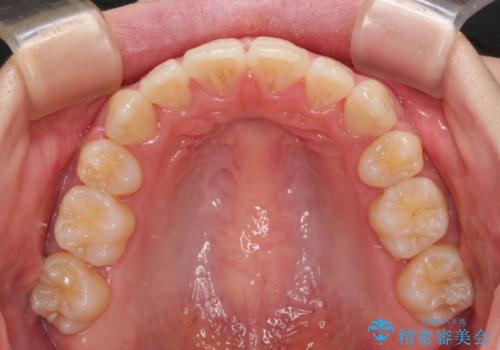

- メタルブラケット

- 1年9ヶ月

上下ともに歯列が前方に突出していたため、上下左右の第一小臼歯4本を抜去し、ワイヤー装置による矯正治療を行うこととしました。

上下左右4本抜歯する場合には、通常2年から2年半ほどの期間を要しますが、舌のトレーニングをしっかりと行っていただいたことで、1年9ヶ月で終了することができました。